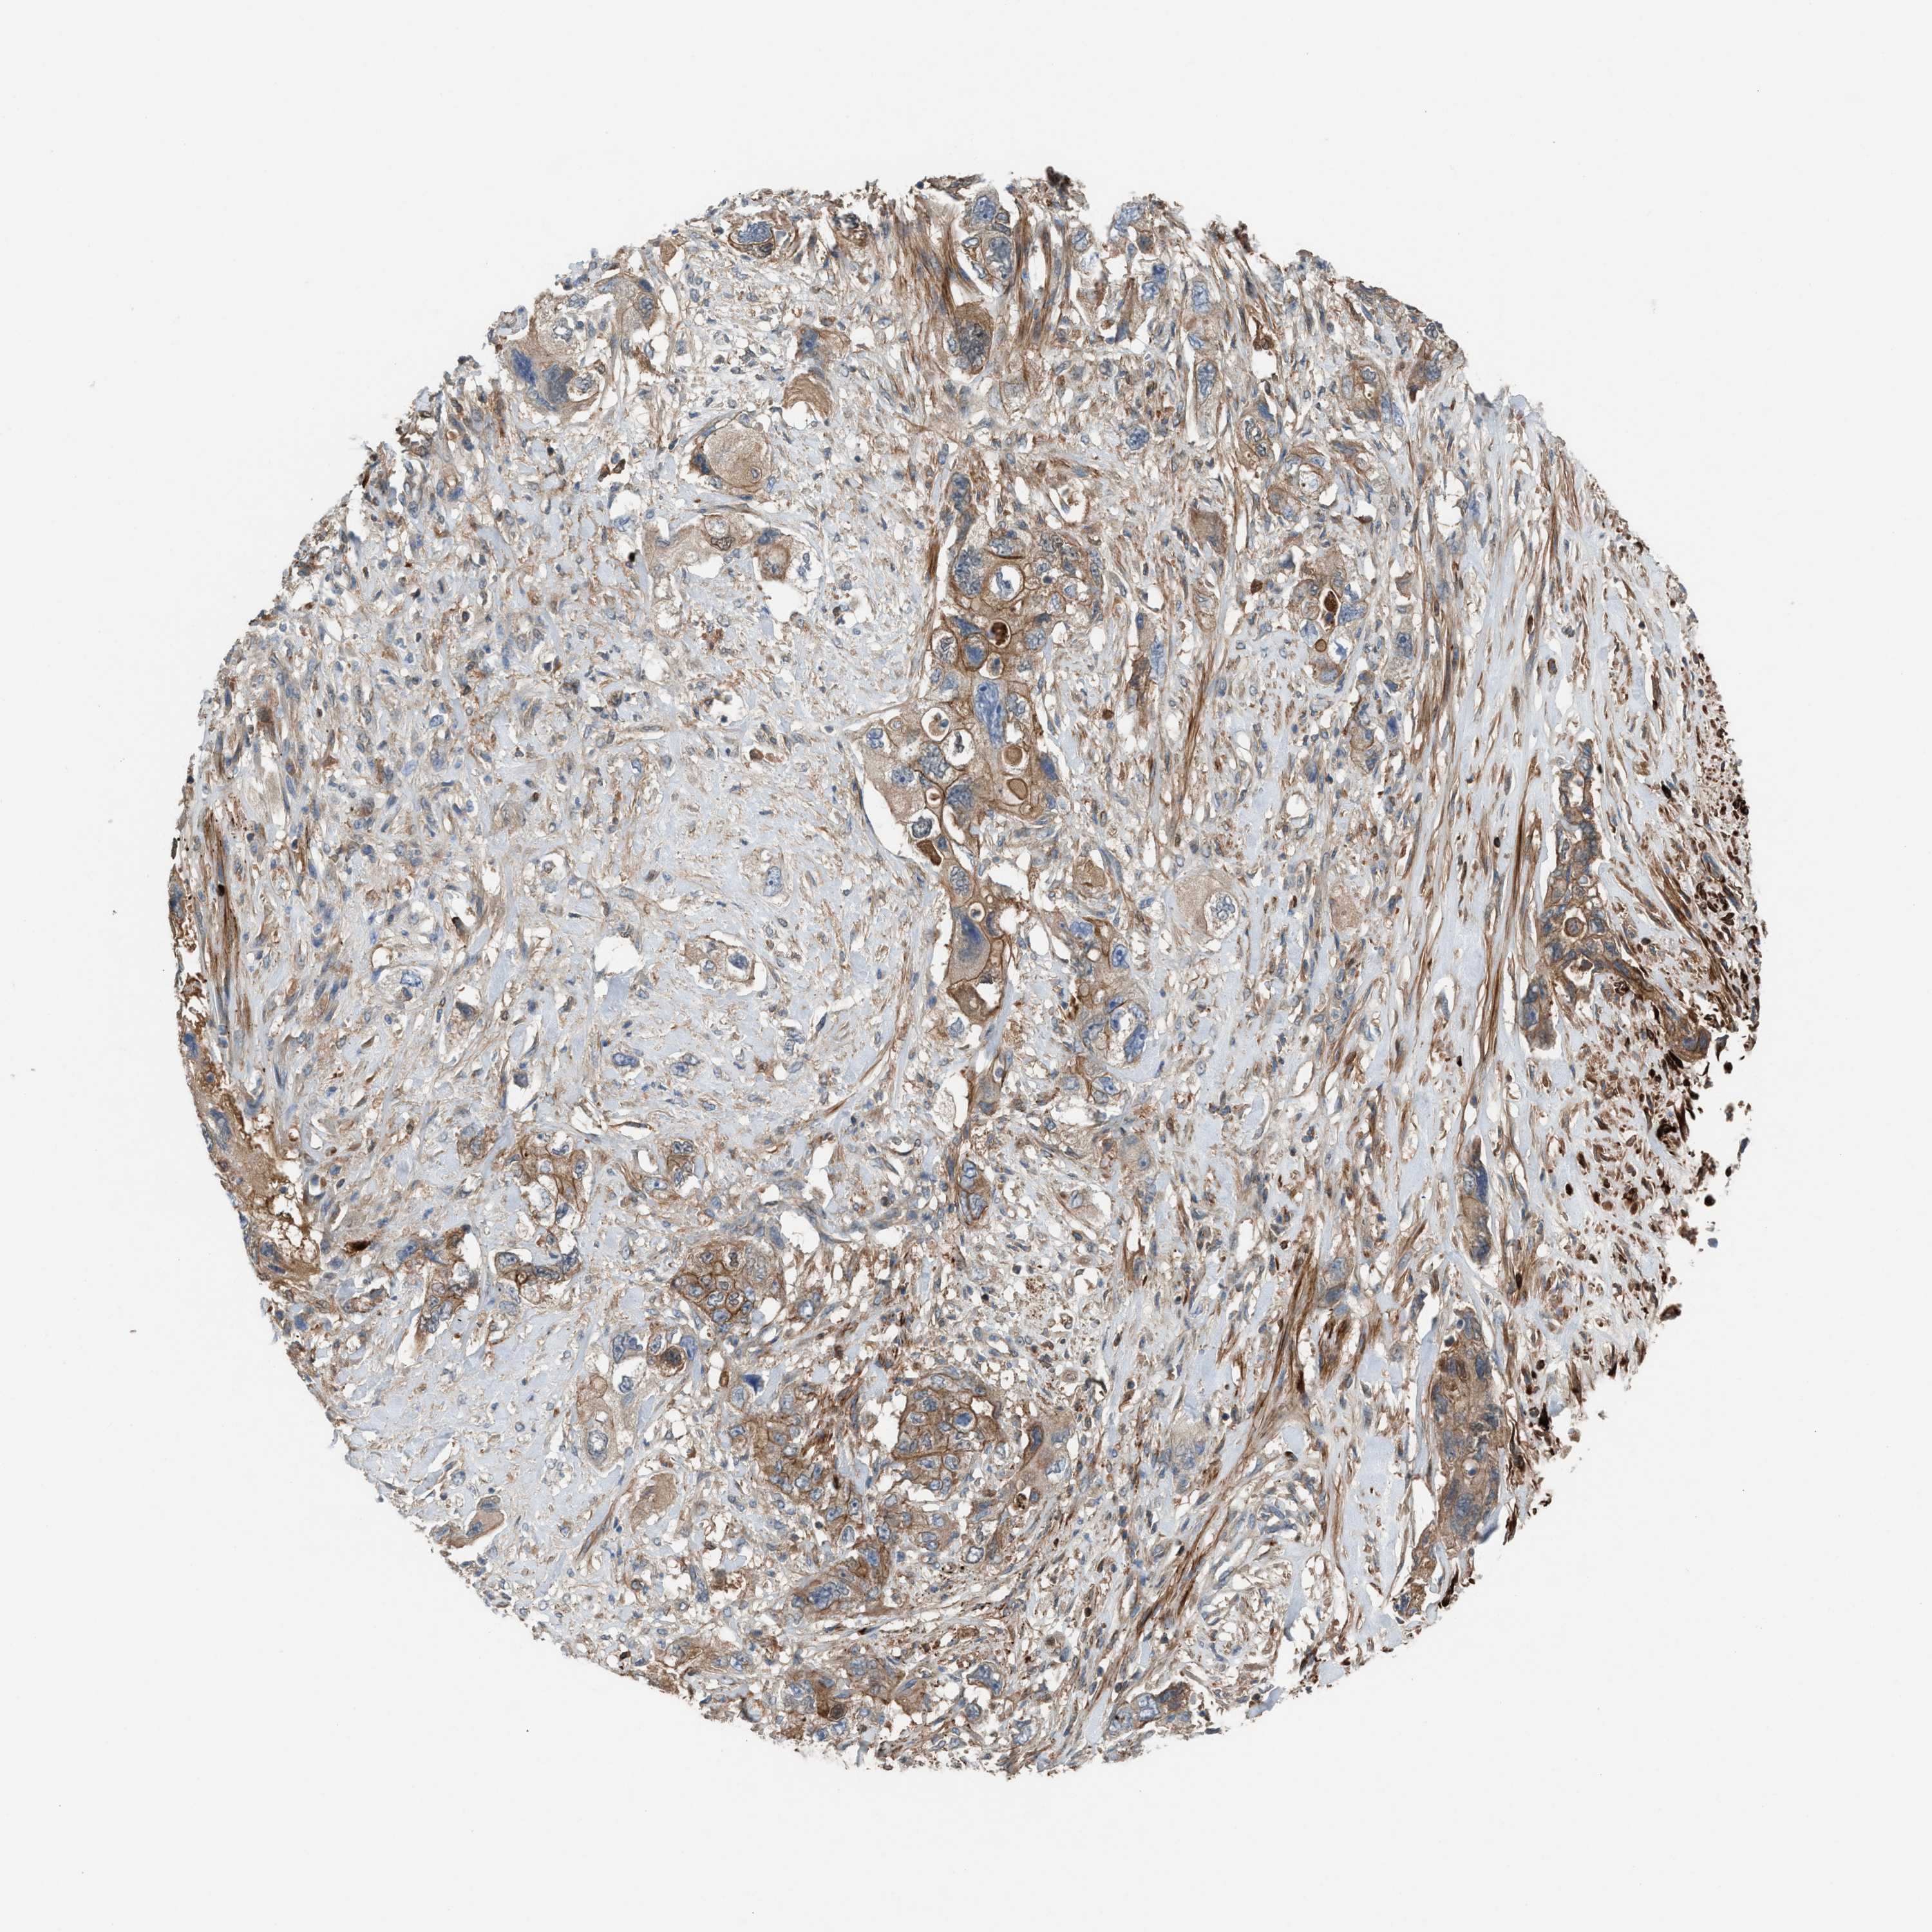

PANCREATIC CANCER - Protein expressioni

A mouse-over function shows sample information and annotation data. Click on an image to view it in a full screen mode. Samples can be filtered based on level of antibody staining by selecting one or several of the following categories: high, medium, low and not detected. The assay and annotation is described here.

Note that samples used for immunohistochemistry by the Human Protein Atlas do not correspond to samples in the TCGA dataset.

Antibody stainingi

Antibody staining in the annotated cell types in the current human tissue is reported as not detected, low, medium, or high, based on conventional immunohistochemistry profiling in selected tissues. This score is based on the combination of the staining intensity and fraction of stained cells.

Each image is clickable and will lead to virtual microscopy that enables deeper exploration of all samples and also displays staining intensity scores, fraction scores and subcellular localization as well as patient and tissue information for each sample.

Antibody HPA021545

Antibody HPA021849

Staining

High

Medium

Low

Not detected

Intensity

Strong

Moderate

Weak

Negative

Quantity

>75%

75%-25%

<25%

None

Location

Nuclear

Cytoplasmic/membranous

Cytoplasmic/membranous,nuclear

Adenocarcinoma, NOS